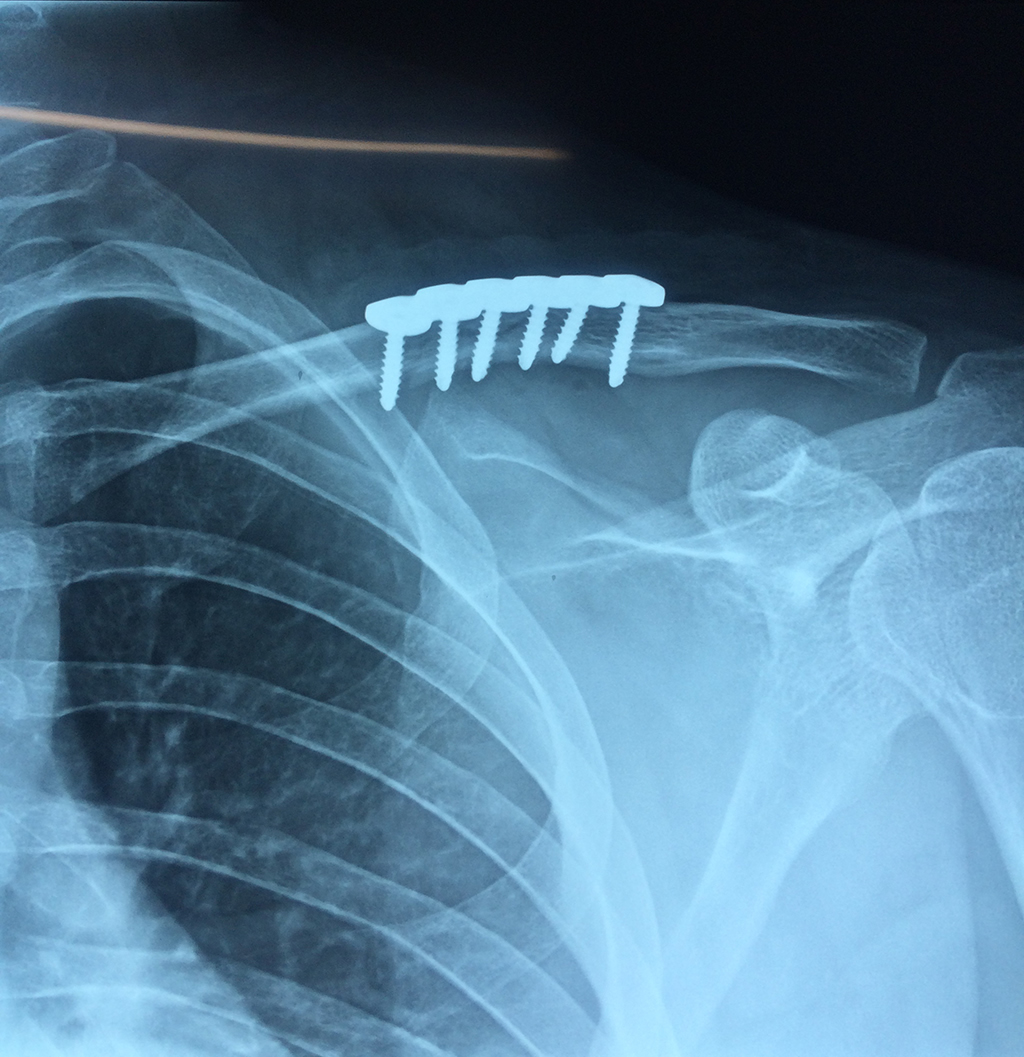

La clavícula es un hueso largo, con forma de "S" itálica, situado en la parte anterosuperior del tórax. Junto con la escápula forman la cintura escapular. Se puede palpar por toda su longitud y se extiende del esternón al acromion de la escápula, siguiendo una dirección oblicua lateral y posterior.